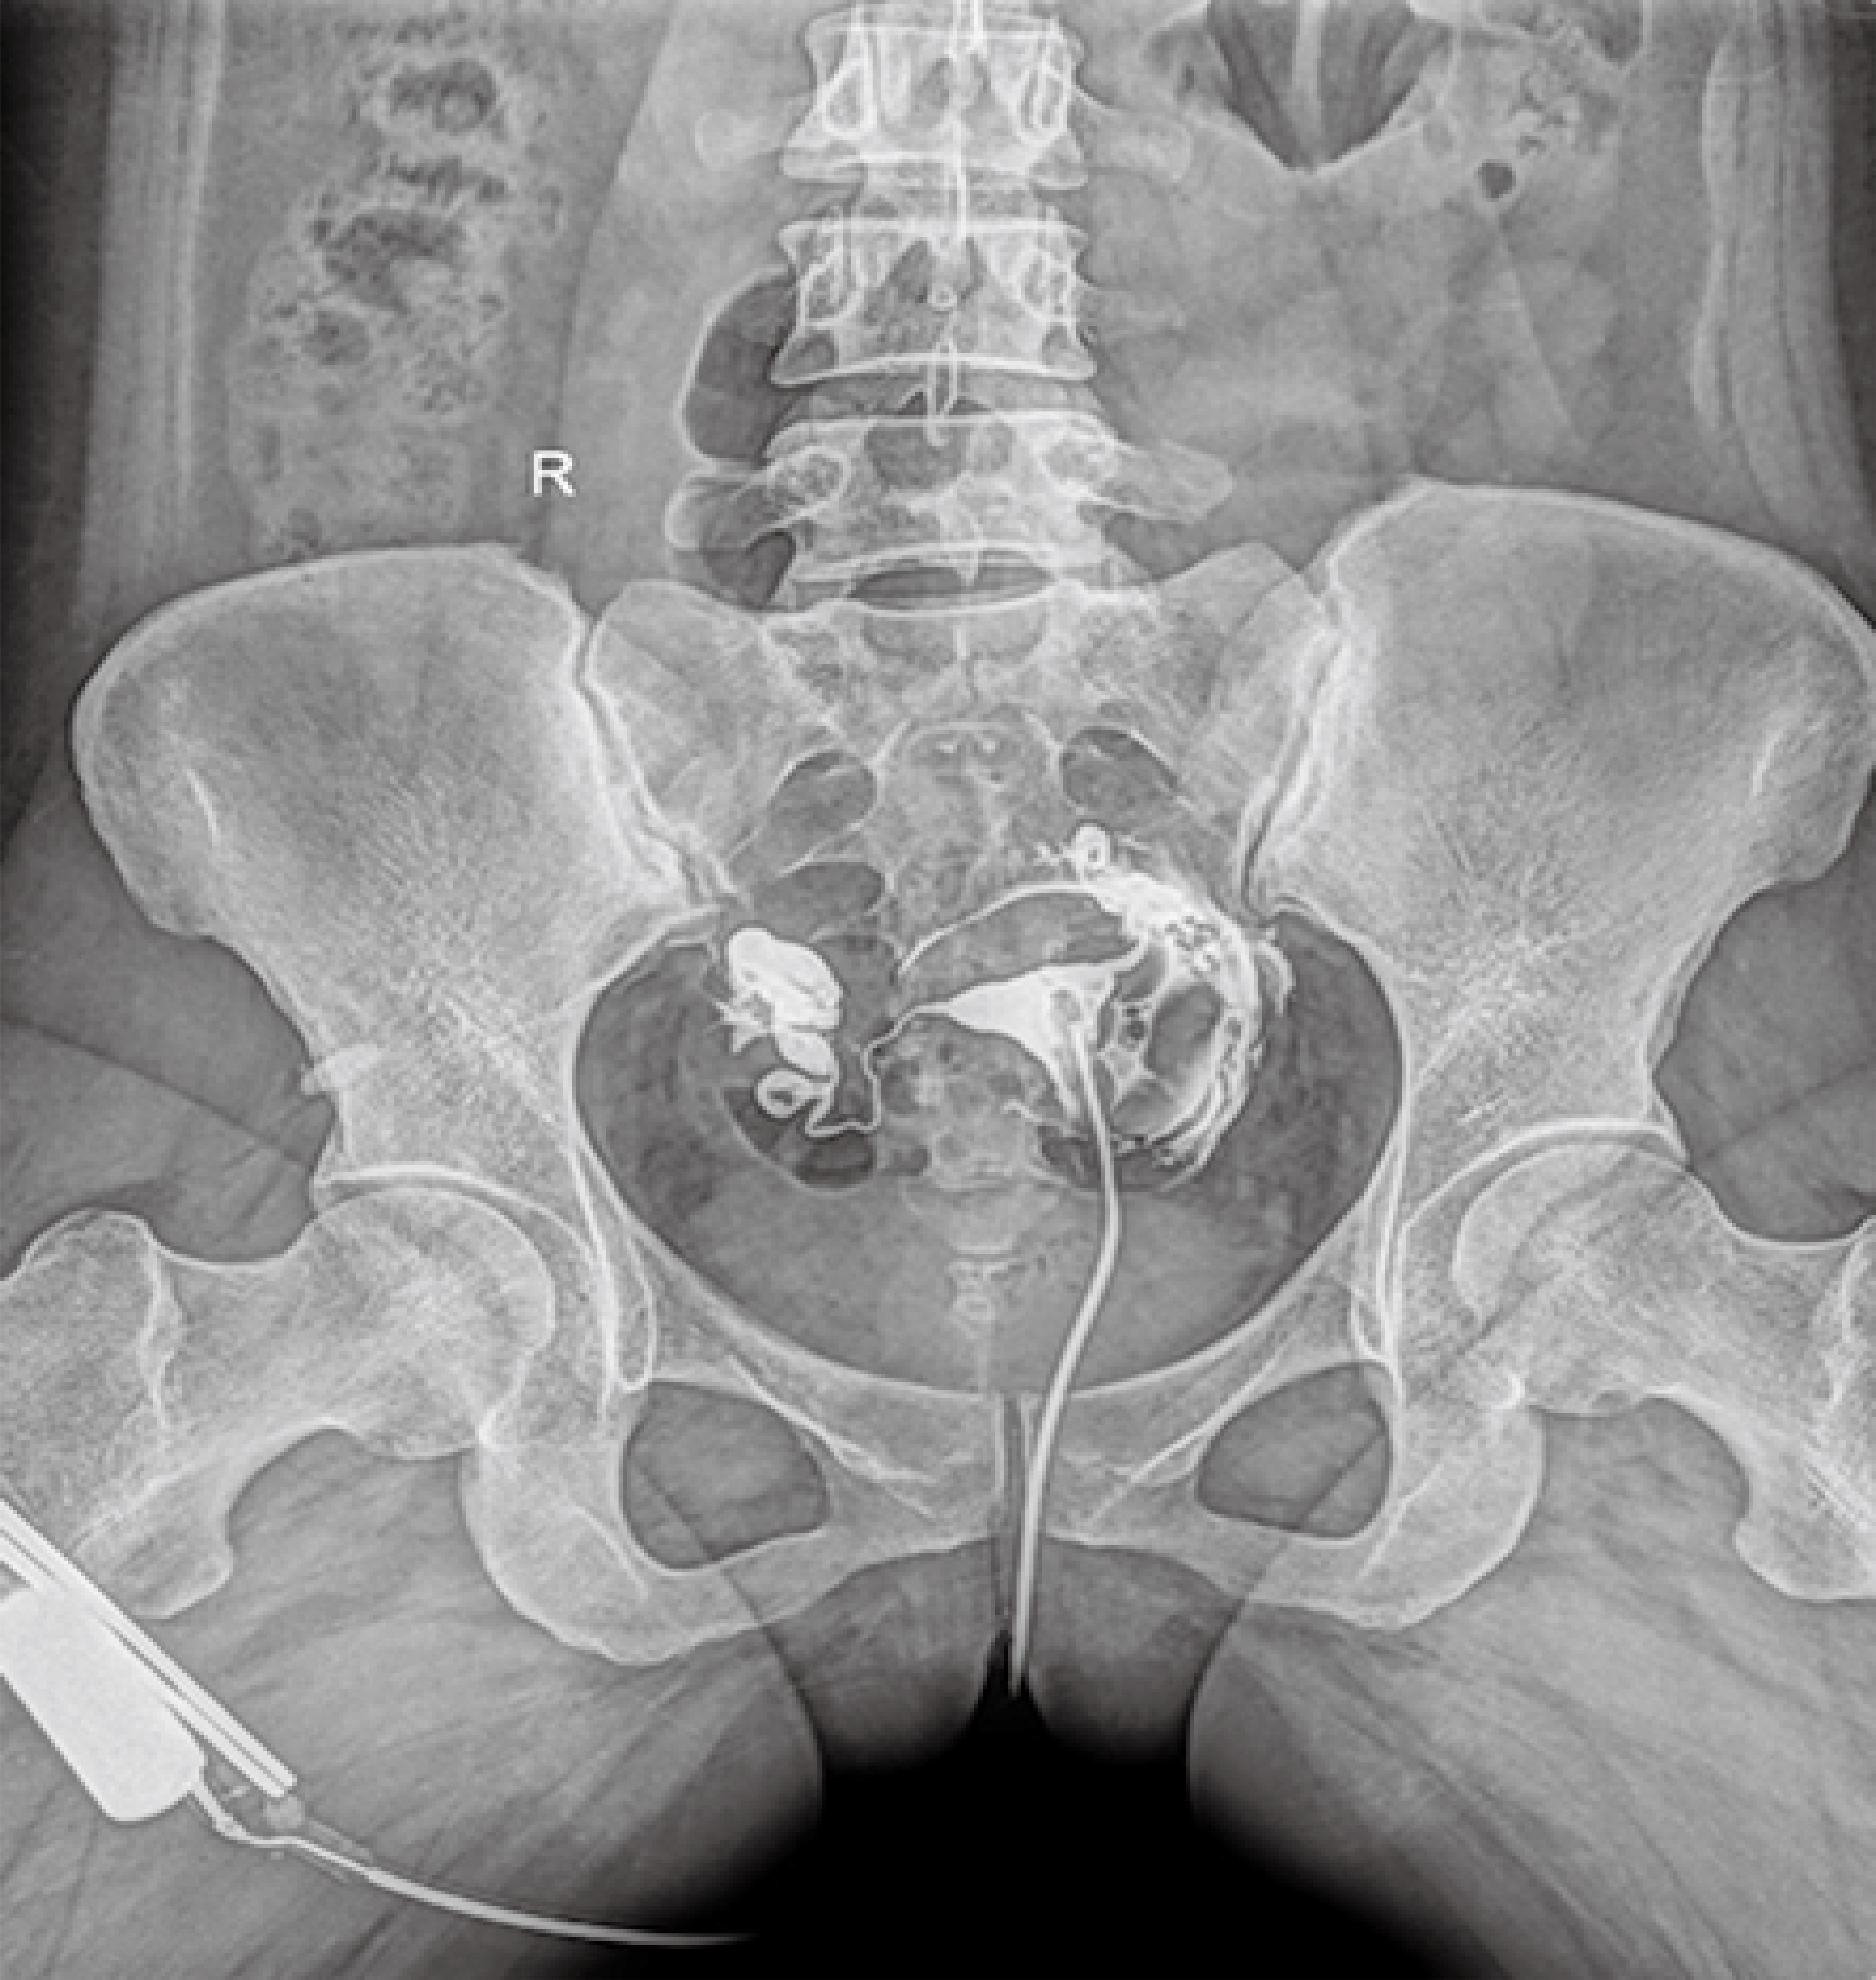

普利德醫(yī)療自主研發(fā)的新一代數(shù)字化X線透視攝影系統(tǒng),可應(yīng)用于DR攝影、數(shù)字透視、數(shù)字造影以及可視化精準(zhǔn)DR拍片等多種臨床X線檢查領(lǐng)域。

● 最高幀速可達(dá)30幀/秒,動(dòng)態(tài)采集清晰流暢,避免漏診、誤診情況的發(fā)生;

● 在可視過(guò)程或回放過(guò)程中,如發(fā)現(xiàn)疑似病灶,可進(jìn)行毫秒級(jí)高清點(diǎn)片,隨時(shí)抓取單幀圖像,精準(zhǔn)捕抓病灶。